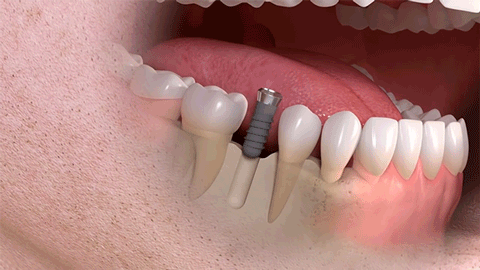

單顆牙種植

多顆牙種植

相比傳統(tǒng)固定義齒和活動(dòng)義齒,種植牙是醫(yī)學(xué)界公認(rèn)的理想修復(fù)方式,被譽(yù)為“人類的第三副牙”。相比活動(dòng)假牙不舒服、難清洗、容易引起口腔黏膜病變,種植牙更穩(wěn)固耐用,舒適美觀,咀嚼功能好,一次種植,即可重獲好口福!種植牙不僅是中老年人的專利,年輕人因意外、牙病等造成的單顆、多顆牙齒缺失,也能夠通過(guò)種植牙進(jìn)行修復(fù)調(diào)節(jié),重獲幸福笑容。